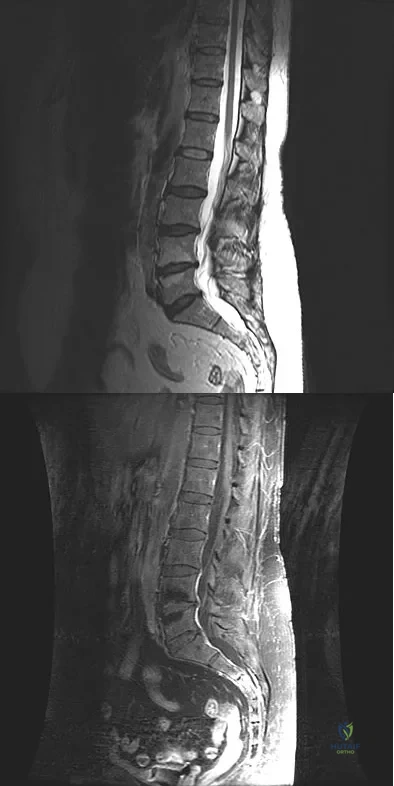

A patient who underwent a L4-L5 hemilaminotomy and partial diskectomy for radiculopathy 8 weeks ago now reports increasing low back pain without neurologic symptoms. A sagittal T2-weighted MRI scan is shown in Figure 13a, and a contrast enhanced T1-weighted MRI scan is shown in Figure 13b. What is the most appropriate management for the patient's symptoms?